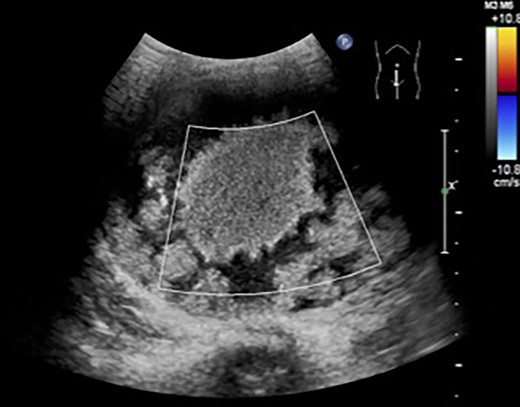

The patient was a 10-year-old girl. She visited our hospital after her grandmother noticed a mass in her lower abdomen that she had been aware of for 6 months. Abdominal ultrasonography revealed that she had a large mass centered in her lower abdomen. The tumor border was clear, the internal structure was heterogeneous and the blood flow was poor (Fig. 1). We suspected an ovarian tumor, but blood tests showed no elevated tumor markers such as AFP and CA19–9. Abdominal magnetic resonance imaging revealed a cystic mass 10 cm in diameter with high intensity on T1-weighted images and high intensity on T2-weighted images (Fig. 2). Abdominal computed tomography revealed a spleen near the navel and a cystic lesion with poor contrast that continued from the lower pole of the spleen (Fig. 3).

Abdominal computed tomography revealed a spleen (arrows) near the navel and a cystic lesion with poor contrast that continued from the lower pole of the spleen.